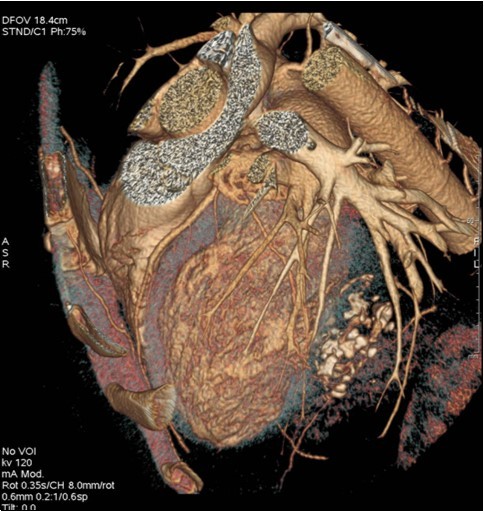

The 64-slice computed tomography (CT) showed a left ventricle intra-myocardial mass of tissue density (25 HU), not enhancing after injection of contrast, and containing multiple central and peripheral arciform calcifications (Figure 3,Figure 4,and Figure 5).

Figure 5.Coroscanner with three-dimensional reconstruction: intra-myocardial mass of left ventricle with multiple calcifications.